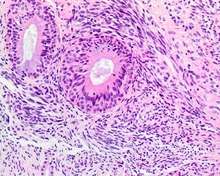

* Infiltrative, highly cellular spindled cell neoplasm that is poorly circumscribed and unencapsulated. Bone destruction or invasion is common. The cells show medium to long fascicles, with a herringbone pattern. The cells are remarkably uniform with elongated nuclei. There are delicate strands of intercellular collagen without ropy or dense deposition. There is a very characteristic concurrent surface-type respiratory epithelial proliferation invaginated from the surface or in small cystic spaces within proliferation, often forming glands.

The background may have a rich vascularity and usually has a small number of scattered lymphocytes. Mitoses are rare, while necrosis, ulceration and hemorrhage are usually absent.

S100 protein reaction in a biphenotypic sinonasal sarcoma. - Smooth muscle actin or muscle specific actin seen in nearly all tumors, but strong and diffuse reaction with SMA is seen in only about 50% of cases.